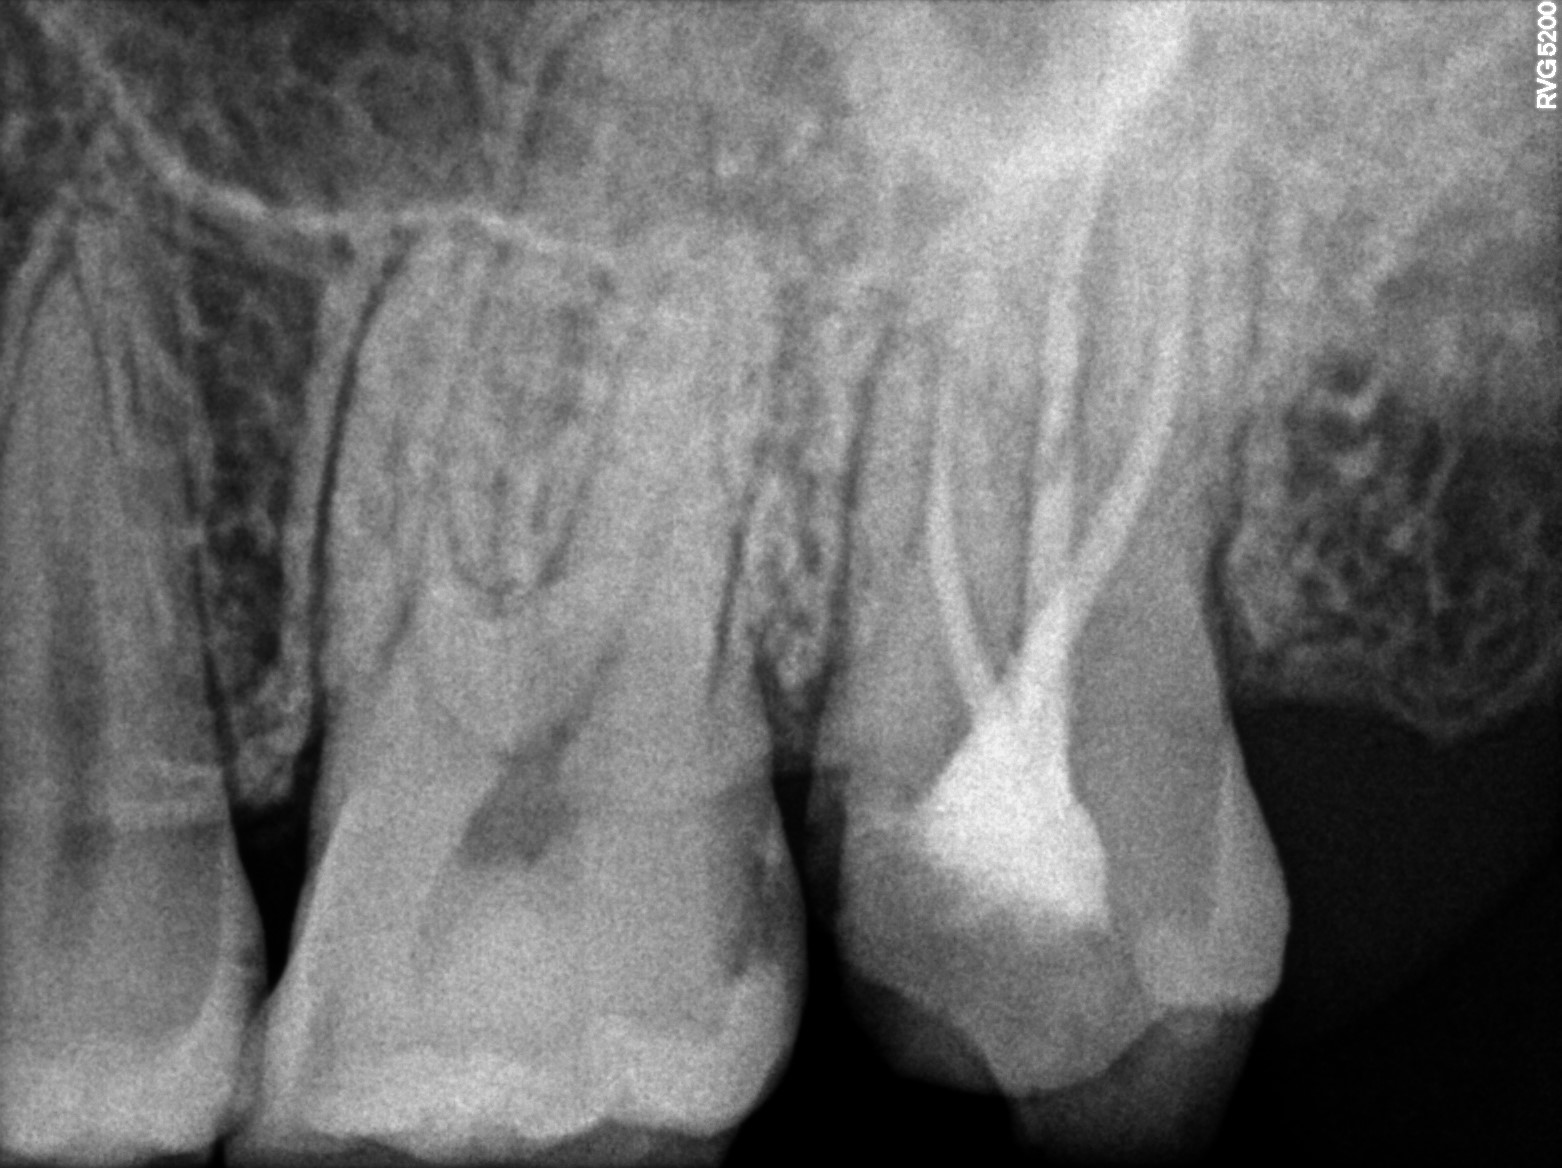

Dental Radiographs FHIR: DocumentReference · LOINC 24641-7

xray_1744445837.jpg

24641-7

| Root canal treatment | 234780006 | D3330 Endodontic therapy, molar tooth | ##27 | 2025-04-12 | completed | dtech done with 27,adv-metal endocrown with 27 if no pain |

| Dental pulp necrosis | — | 234946006 | resolved | 2025-04-12 | dtech done with 27,adv-metal endocrown with 27 if no pain |